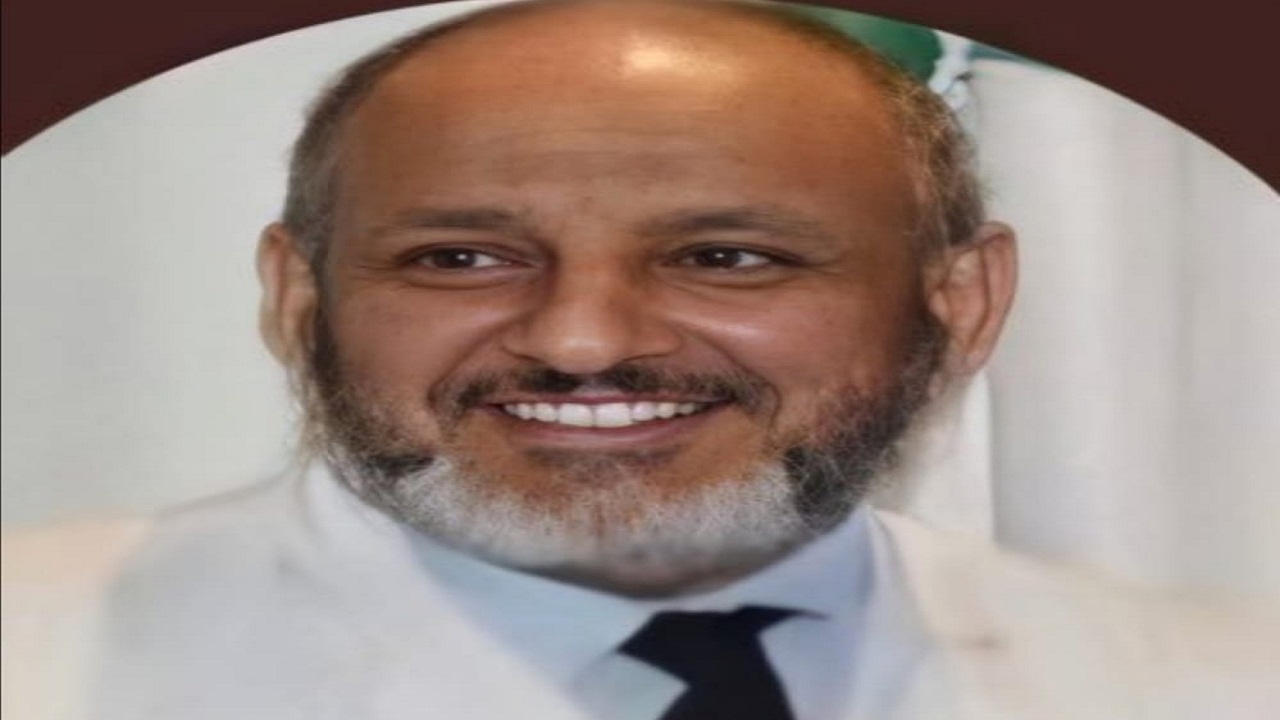

الخضيري: التدخين يؤذي لاضطراب أحماض المعدة

بالفيديو.. الخضيري يتحدث عن فوائد التدخين المزعومة وصناعة الوهم